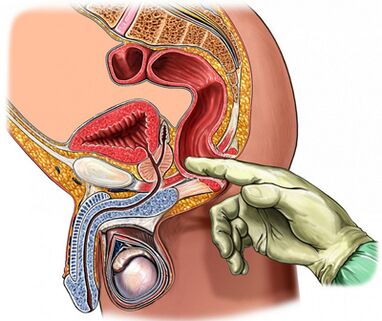

Palpation der Prostata

Von vorrangiger Bedeutung für die Diagnose der Krankheit ist das Abtasten der Prostata, das während der Exazerbationsphase zunimmt und während der Abschwächung des Entzündungsprozesses abnimmt. Bei chronischer Prostatitis schwillt die Drüse während der Exazerbationsphase an und schmerzt.

Die Konsistenz des Organs kann unterschiedlich sein: Erweichungs- und Verhärtungsbereiche werden abgetastet, Retraktionsbereiche bestimmt. Durch Abtasten ist es möglich, die Form der Drüse, den Zustand der Samenhöcker und des umgebenden Gewebes zu beurteilen.

Der Prozess der transrektalen digitalen Untersuchung wird mit der Sammlung von Drüsensekreten kombiniert. Manchmal ist es notwendig, das Sekret aus jedem Lappen separat zu entnehmen.

Der „Goldstandard“ bei der Diagnose einer chronischen Prostatitis sind:

- Sammeln der ersten Urinportion.

- Sammlung der zweiten Urinportion.

- Gewinnung von Drüsensekreten durch Massage.

- Sammlung der dritten Urinportion.

Anschließend erfolgt eine mikroskopische und bakteriologische Untersuchung des Materials.